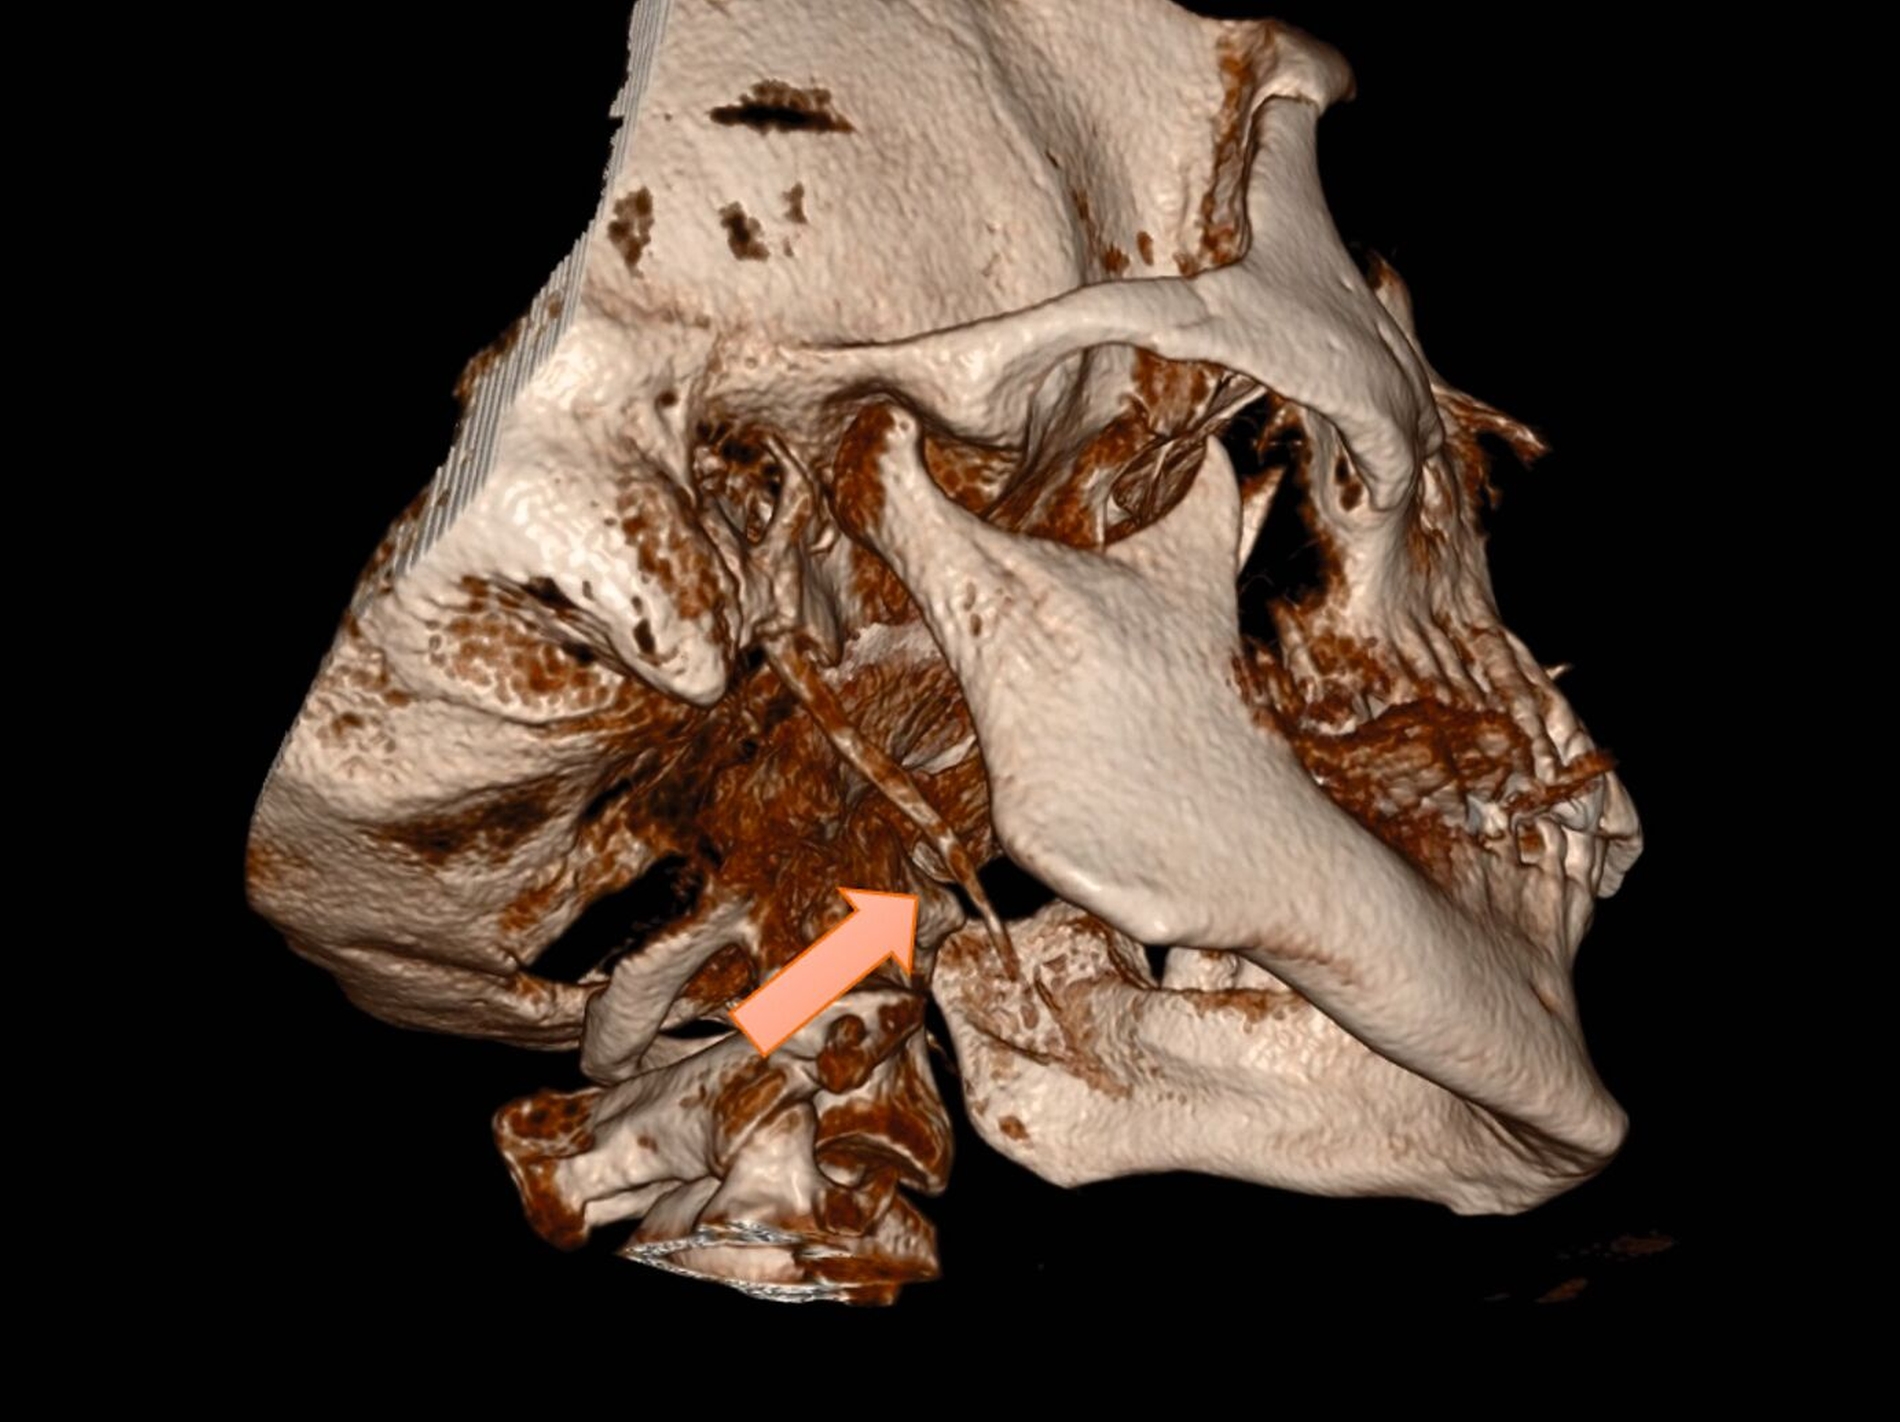

Die klinische Untersuchung ergab keine Hinweise auf Sensibilitätsstörungen, eine Fazialisparese oder Hirnnervenausfälle. Allerdings war die Palpation des rechten Kieferwinkels schmerzhaft, insbesondere bei der intraoralen Untersuchung der Tonsillenloge. Eine mechanische Provokation durch Kopfdrehung und Palpation verstärkte die Beschwerden. Die prothetisch versorgten Zähne zeigten keine pathologischen Befunde. Zur weiteren Diagnostik wurde eine Digitale Volumentomografie (DVT) mit 3D-Rekonstruktion durchgeführt. Diese bestätigte die im OPG vermutete Diagnose eines beidseitig elongierten Processus styloideus, mit einer stärkeren Ausprägung auf der rechten Seite (Abbildung 2).

Die klinischen Beschwerden korrelierten mit der radiologisch festgestellten Asymmetrie. Nach ausführlicher Aufklärung über konservative und operative Therapieoptionen entschied sich die Patientin aufgrund der deutlichen Symptomatik für eine chirurgische Resektion des elongierten Processus styloideus auf der rechten Seite. Der Eingriff wurde über einen extraoralen Zugang durchgeführt, um eine bessere Übersicht und die sichere Entfernung des verlängerten Processus zu gewährleisten. In Intubationsnarkose erfolgte die piezochirurgische Resektion des ossifizierten Ligamentum stylohyoideum am Processus styloideus über einen zervikalen Zugang (Abbildungen 3 bis 6); der ebenfalls verlängerte linke Ligamentum stylohyoideum wurde manuell von enoral frakturiert.

Die Diagnostik des Eagle-Syndroms basiert auf einer Kombination aus Anamnese, klinischer Untersuchung und bildgebenden Verfahren. Als Erstuntersuchung ist ein OPG geeignet, liefert jedoch keine detaillierten Informationen über die räumliche Lage des verlängerten Processus styloideus. Daher gilt die dreidimensionale Bildgebung (CT oder DVT) als Goldstandard, um die exakte Länge und die Beziehung zu den angrenzenden Strukturen zu bestimmen [Mortellaro et al., 2002]. Differenzialdiagnostisch müssen Kiefergelenkpathologien, eine Trigeminusneuralgie und psychosomatische Ursachen ausgeschlossen werden, was jedoch durch eine bildgebende Diagnostik zuverlässig möglich ist [Kozakovičová et al., 2023].

Die CT oder die DVT mit 3D-Rekonstruktion sind der diagnostische Goldstandard, da sie eine präzise Beurteilung der Länge und der Lage des Processus styloideus ermöglichen.